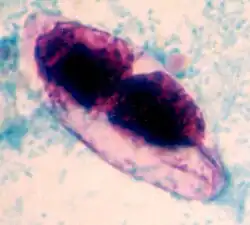

| strained oocyst of Cystoisospora belli | |

A fully mature (sporulated) oocyst of genus Isospora is a spindle-shaped body that has two sporocysts that contain four sporozoites each.[4]

The oocysts of Cystoisospora belli are long and oval shaped. They measure between 20 and 33 micrometers in length and between 10 and 19 micrometers wide.[5]

Cystoisospora belli is diagnosed by identification of the oocyst through examining a stool sample under a microscope. The diagnostic stage is the immature oocyst that contains a spherical mass of protoplasm. In other words, the oocyst that is diagnosed in the stool sample is unsporulated, and contains only one sporoblast.[2] For stool diagnosis, direct smear, concentration smear, microscopic wet mount, or iodine stains of fecal smears are adequate. But for easy screening, acid-fast stains is recommended.[2][3] If stool test is negative, and biopsies of the small intestine is performed, different stages of schizogony and sporogony should exist in the epithelial cells, but the alteration of the villi is not necessarily present.[2]